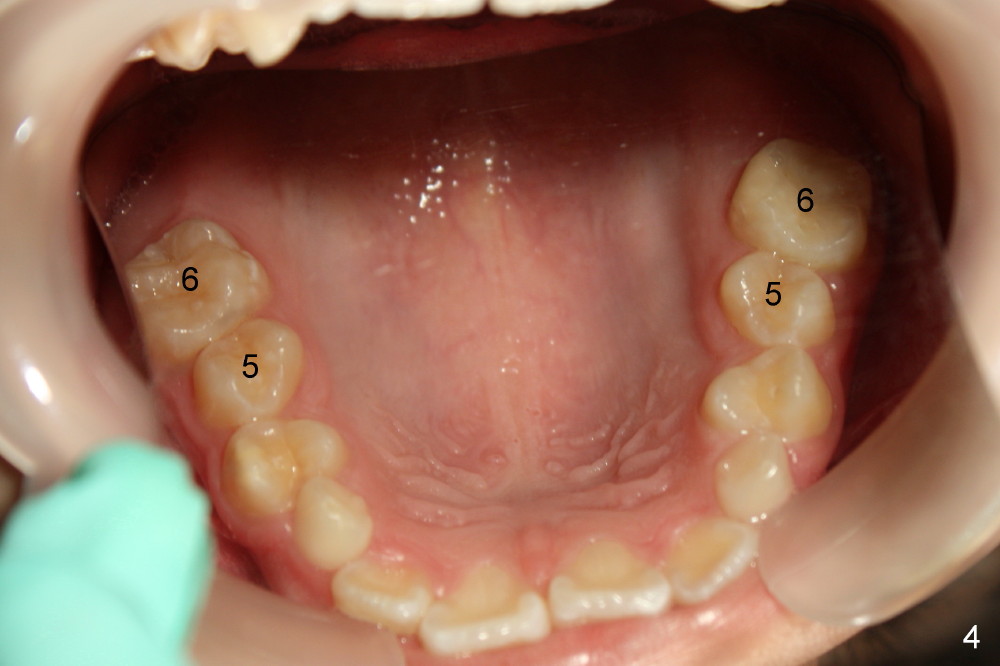

8. Every visit change lower wires until rectangular wires for lower, later as an anchorage to retract u3s downward (Fig.9 preop pan)